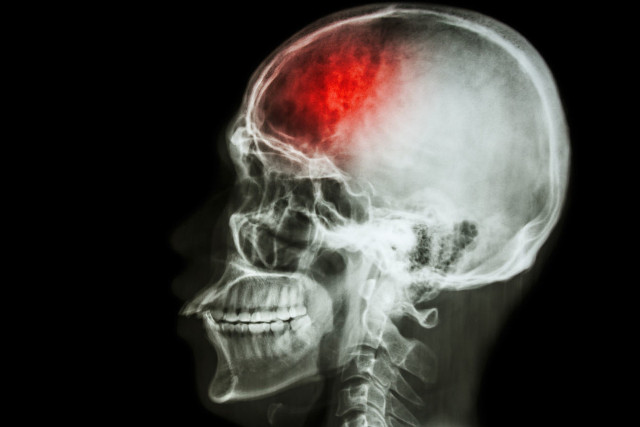

Stem cells help patch brain damage in stroke victims

Researchers at the University of Georgia have developed new stem cell-based treatments for stroke. When tested on animal models, this technique shows that it can reduce brain damage and help the brain to heal faster.

According to the CDC, stroke affects nearly 800,000 people each year in the US, and about 140,000 die, thus making it the fifth cause of death in the country.

Survivors need a long time to recover, and in severe cases, permanent brain damage may occur. Previous studies on stroke treatments may include anti-inflammatory drugs, peptides found in spider venom and catheters to remove blood clots.